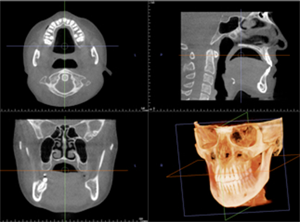

レントゲン撮影・CT撮影・口腔内Scan ・シュミレーションソフトによるプランニング

インプラント予定部位の骨の状態、周囲組織の状態を診査します。CTを用いることで多角的に診断することができます。当院では最新の歯科用コーンビームCTを設置し、低被爆を実現しています。

全身状態の把握をするため、問診、血液検査、生体モニターによるバイタルのチェック等、またインプラントを埋入する骨の状態、その後のかみ合わせを考慮した方向性や周辺組織の状態を確認するため、レントゲン撮影及びCT撮影を行いシュミレーションソフトを使用使用し、総合的に治療計画を立案していきます。また、必要に応じて近隣医療機関との連携を行います。

当院では最新のドイツKavo 社製のCTを設置しています。

低被爆で細かな診断と埋入シュミレーションを行い診断をしております。

シュミレートした画像をお示ししながら検査結果と治療計画をご提案し、ご質問にお答えします。

当院使用のCT装置について

当院ではドイツKaVo社 3D eXamを使用し、低被ばくで高精度の撮影と解析を行っています。

歯科用CTは低被爆で高精細な画像が得られます。

このためインプラント治療の診断、プランニングのみならず精密根管治療や歯周病治療など様々な治療で使用しています。